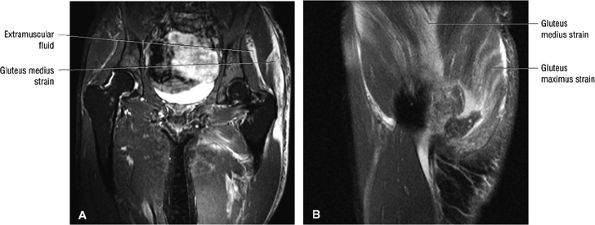

FIGURE 3.30 ● Normal sagittal anatomy of the hip. (A and B) On medial sagittal images, the course of the obturator internus, piriformis, and the adductor muscles can be followed and analyzed for strain injury or tears. (C and D) Tendinosis and tears of the common hamstring tendon origin on the ischial tuberosity are optimally viewed at this location and are extremely common in middle aged and elderly patients. (E and F) Although thinning and fraying of the articular cartilage can occur anywhere in the joint, chondral degeneration is most commonly seen first in the anterior superior quadrant, often accompanied by anterior labral tears, subchondral edema, and cystic change in the anterior acetabulum. When any one of these findings is present, a careful search for the others should be performed. (G and H) Linear tears of the anterior labrum can be mimicked by fluid filling a normal recess between the anterior labrum and the anterior joint capsule. Imaging in the axial and coronal planes is used to distinguish between a true tear and the normal recess, since a tear is visualized and confirmed in the axial and coronal planes, whereas a recess is only seen prominently in the sagittal plane. (K and L) The gluteus medius and minimus tendons have been referred to as the “rotator cuff” of the hip. The gluteus medius tendon inserts posteriorly on the greater trochanter, and the gluteus minimus tendon inserts anterolaterally on the greater trochanter. (I and J) Loose bodies commonly lodge in the joint recesses anterior and posterior to the femoral neck (deep to the iliofemoral and ischiofemoral ligaments). They are commonly seen (particularly in the sagittal plane) in patients with chondral degeneration. (M and N) Acute tears of the gluteus medius and minimus often mimic symptoms of a proximal femoral fracture. Chronic partial tears and tendinosis are frequently associated with trochanteric bursitis, and are common in middle-aged and elderly patients.